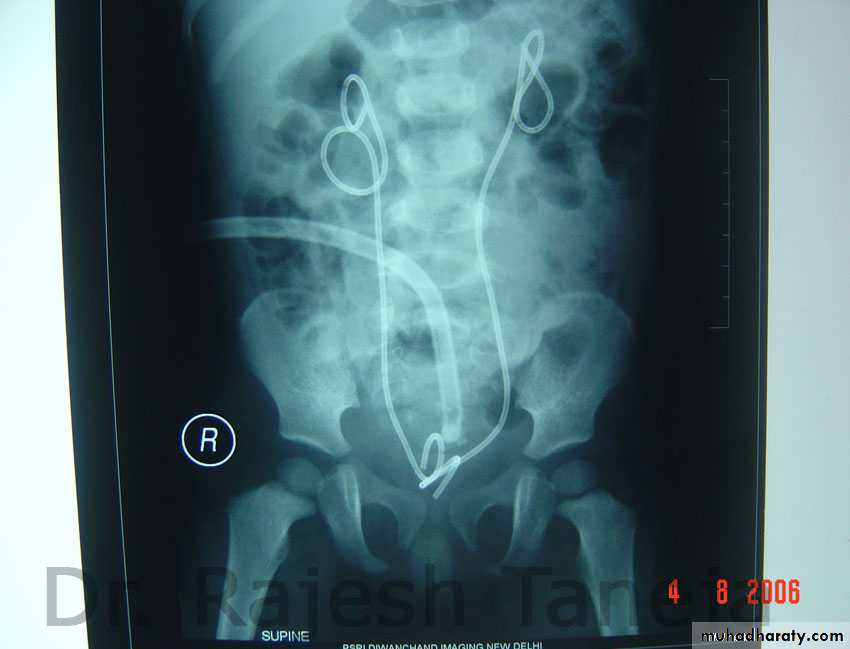

x-ray finding.

Excretory urograms are usually normal unless refluxhas occurred, in which case hydronephrosis is found.

The accompanying cystogram reveals a bladder of

small capacity, reflux into dilated upper tract may be

noted on cystography.